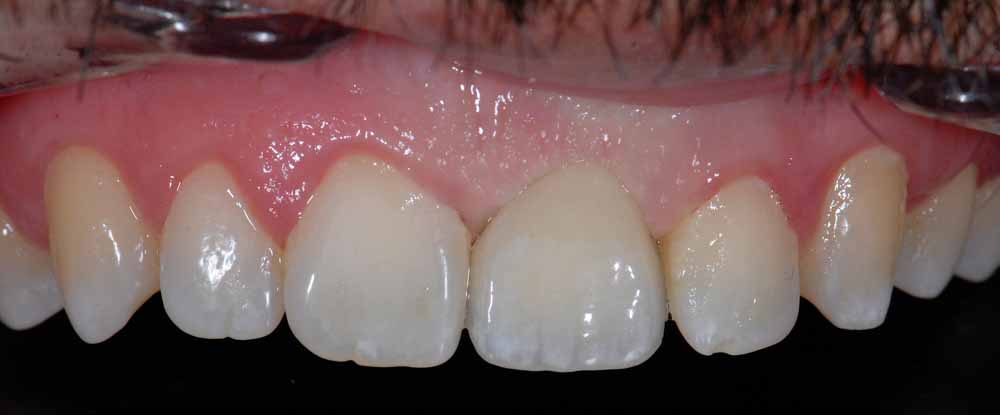

Case Study 1

Missing Tooth

Gap restored with an implant